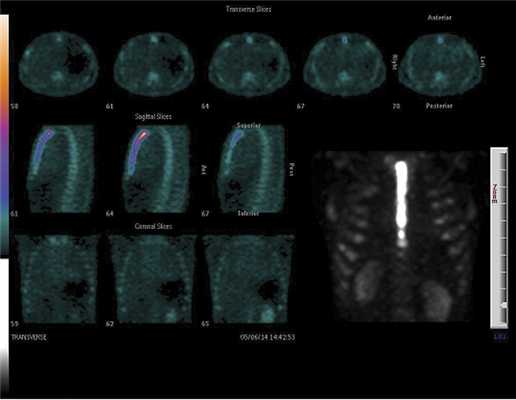

Всем больным в послеоперационном периоде проводили комплексное обследование, направленное на изучение влияния двух методик стернотомии на репарацию грудины и частоту осложнений, связанных с доступом. Для оценки влияния холодноплазменной стернотомии на заживление грудины в раннем послеоперационном периоде контролировали частоту осложнений со стороны раны передней грудной стенки (инфекционных и неинфекционных), в среднесрочном периоде (через 4—5 мес после стернотомии), проводили осмотр больных и сбор жалоб, связанных с ранее использованным стернотомным доступом. Также в среднесрочном периоде выполняли спиральную компьютерную томографию и остеосцинтиграфию грудины с использованием однофотонной эмиссионной компьютерной томографии, совмещенной с компьютерной томографией (томограф GE Discovery NM/CT 570C; «GE healthcare», США). Обработку полученных томограмм осуществляли с помощью пакета прикладных программ Xeleris Workstation («GE healthcare», США). При остеосцинтиграфии использовали радиофармпрепарат 99mTc-Технефор («Диамед», Россия).

Проведенная в среднесрочном периоде остеосцинтиграфия грудины с 99 m Tc-пирофосфатом, несмотря на однотипные результаты спиральной компьютерной томографии, показала существенные различия в поглощении остеотропного радиофармпрепарата тканями грудины в группах (рис. 2 и 3), что свидетельствует о разной интенсивности кровотока в зоне распила грудины (табл. 4).

Рис. 2. Остеосцинтиграмма грудины больного основной группы через 4 мес после вмешательства. Поглощение РФП (число импульсов): рукоятка — 90 857, тело — 61 512, мечевидный отросток — 61 198.

Рис. 3. Остеосцинтиграмма грудины больного основной группы через 4,5 мес после вмешательства. Поглощение РФП (число импульсов): рукоятка — 598 399, тело — 441 402, мечевидный отросток — 249 643.

В контрольной группе больных отмечено повышенное по сравнению с основной группой накопление препарата в области рукоятки грудины — в среднем на 45%. В области тела грудины интенсивность накопления была в среднем на 80% выше у больных контрольной группы. Также более интенсивное включение препарата наблюдалось и в области мечевидного отростка (в контрольной группе в среднем на 69% выше). По нашему мнению, такой результат свидетельствует о незавершенности консолидации грудины в среднесрочном периоде, что, по-видимому, связано с большей травмой костной ткани и замедлением процесса регенерации, а также с более длительным течением асептического воспаления в зоне вмешательства.